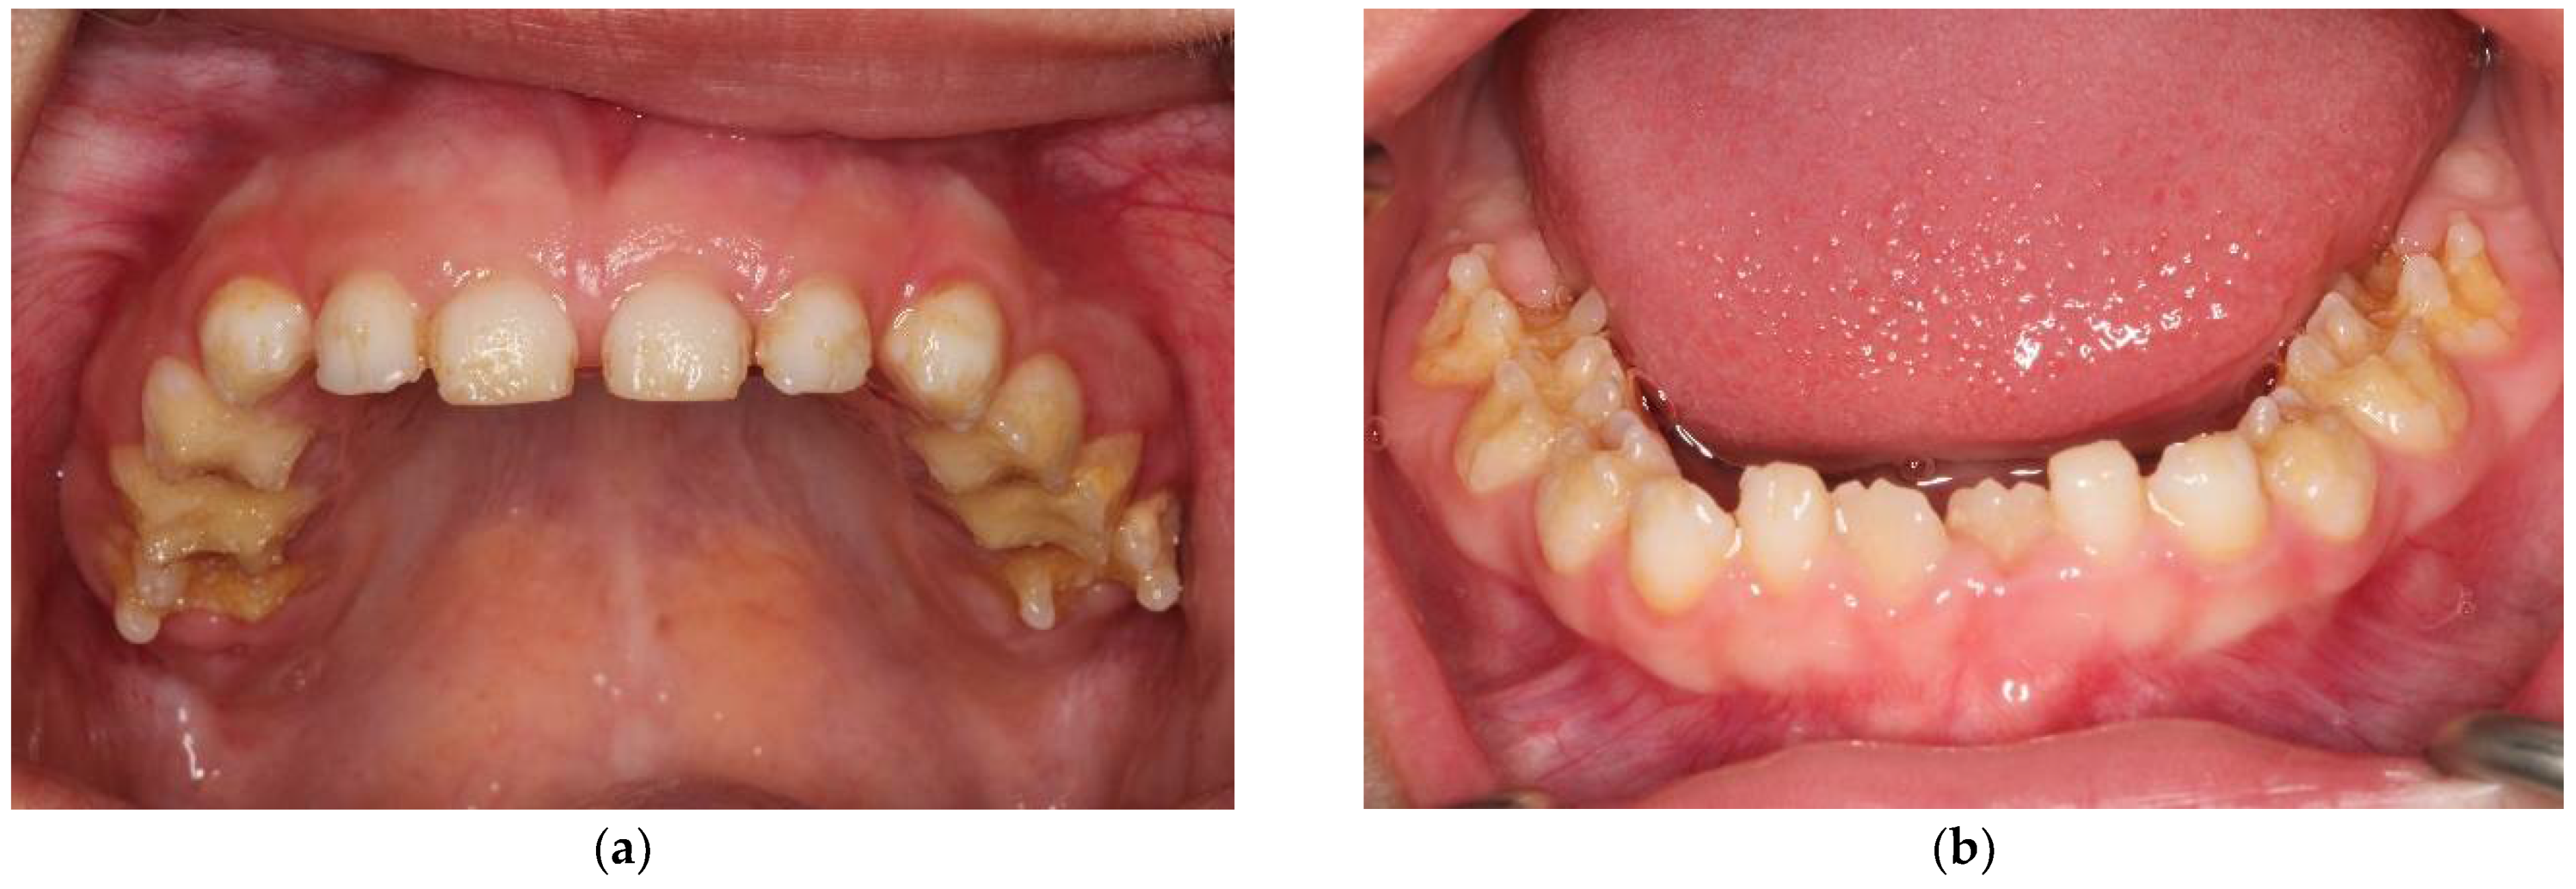

2.1. Case Report 1: Mixed Dentition